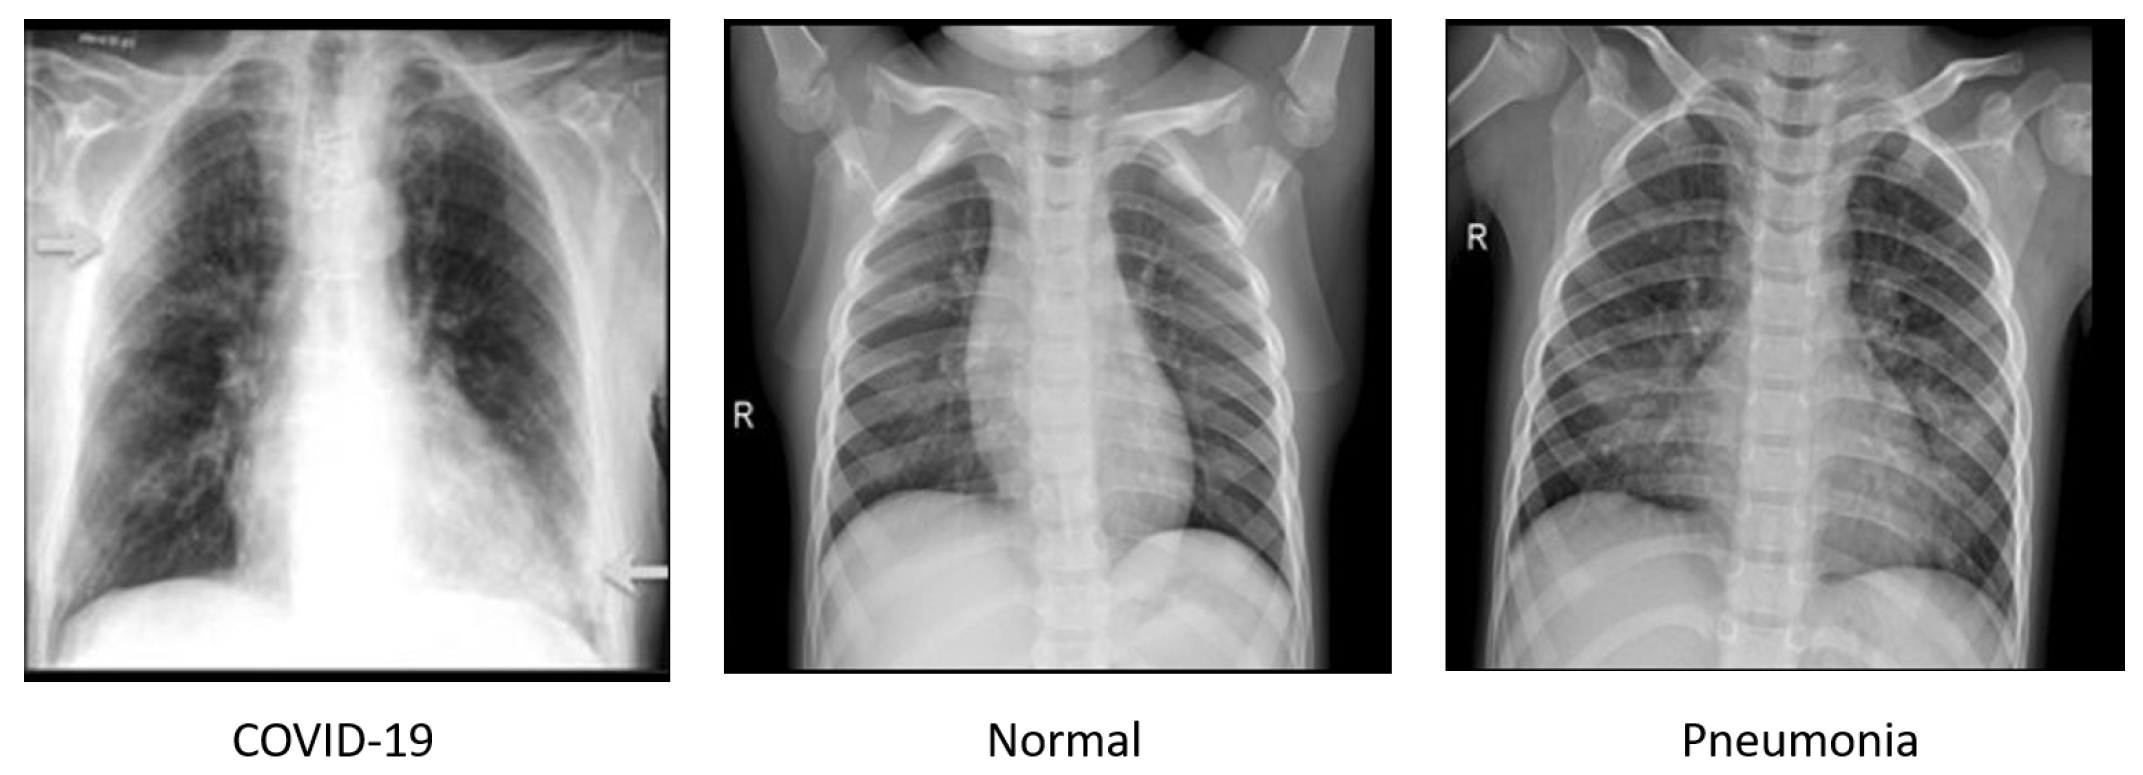

4.1.1. Chest X-ray Dataset